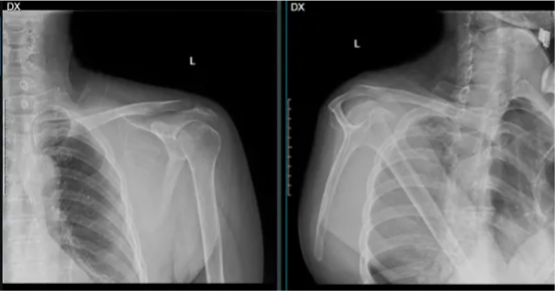

股骨近端包括股骨头、股骨颈以及股骨的粗隆部,是良性肿瘤尤其是瘤样病变的好发部位。主要以孤立性骨囊肿、骨样骨瘤、纤维结构不良等为主。良性肿瘤或肿瘤样病变是最常见的偶然发现的病变,在许多情况下,这些被称作为“沉默的病变”仅需要监视,而不是手术。不过作为负重关节的一部分,股骨的近端需要承受垂直应力及剪切应力,当这些病变位于股骨近端时容易产生病理性骨折,因此手术治疗往往是首选。而传统的手术方式包括刮除植骨内固定、骨水泥填充,极端的情况采用股骨近端关假体置换等,创伤较大,远期并发症如股骨头坏死、局部疼痛.松动翻修等,一直是骨肿瘤医生比较忌惮的手术部位。